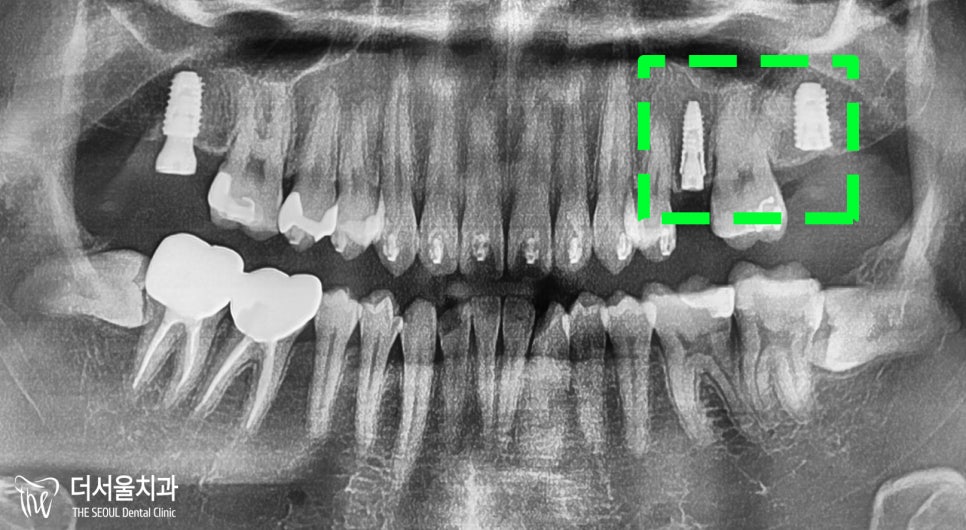

그로부터 6개월이 지났을 때,

17번은 최종 보철까지 다 연결시켰습니다.

나머지 25, 27번은 뼈와 어느 정도 잘 붙어

힐링 어버트먼트를 연결시켜

좀 더 골결합이 잘 이뤄질 때까지 기다려줍니다.

그리고 교합면을 보면,

25, 27번 자리에

최종 보철이 세팅된 것을 볼 수 있습니다.

깔끔히 잘 마무리 되었네요.